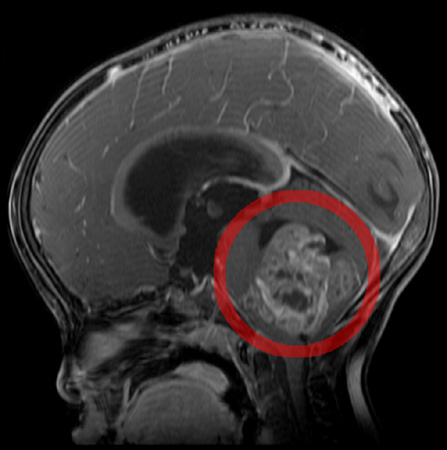

【脳腫瘍】

小児の脳腫瘍は成人と同様で稀な病気であり、人口100万人あたり年間6~7人と報告されています。代表的な小児の脳腫瘍は、神経膠腫、胚細胞腫瘍、髄芽腫、頭蓋咽頭腫、上衣腫があります。

小児脳腫瘍の難しいところは成人と異なり自覚症状が明確でないため、頭の検査を受けるまでに時間がかかることです。画像検査で発見されたときには既に巨大な腫瘍になっていた、ということもよく経験します。

小児脳腫瘍の概要をご説明いたします。

[ 診断 ]

頭部CT・MRI検査を行い、必要があればカテーテル検査なども行います。

確定診断には腫瘍の摘出術を行うことが必要になります。小児の脳腫瘍は術前後の化学療法と放射線治療が極めて重要であり、摘出した病理組織による診断結果によって行う内容が決まります。近年では、腫瘍組織の遺伝子診断を行うことでより効果的な治療法が選択できるようになりました。